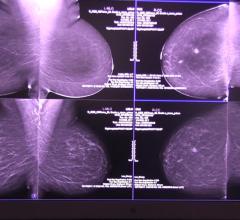

Despite decades of progress in breast imaging, one challenge continues to test even the most skilled radiologists ...

Martin Yaffe, Ph.D., FAAPM, senior scientist, physical sciences/imaging research, Sunnybrook Health Sciences Centre, and ...

Ikonopedia and Konica Minolta Healthcare Americas Inc. showcased integrated breast imaging workflow and reporting at the 103rd Annual Radiological Society of North America (RSNA) meeting, Nov. 26-Dec. 1 in Chicago.

Stamatia Destounis, M.D., FACR, associate professor, University of Rochester School of Medicine, attending radiologist ...